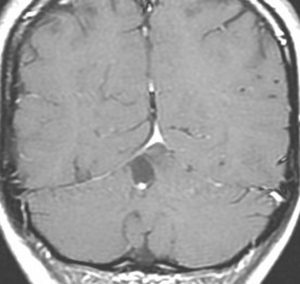

中脳視蓋毛様細胞性星細胞腫 tectal glioma(詳しくはここをクリック)

中脳視蓋グリオーマとして知られるものです。この腫瘍は基本的には,初回手術で全摘出できるのですが,現実的には,技術的に難しすぎるので部分摘出で終えることが多いでしょう。この子は,15歳の時に閉塞性水頭症のために,頭痛,嘔吐,意識障害,瞳孔不同となりました。開頭部分摘出術と第3脳室開窓術で回復して,その後にカルボプラチンとビンクリスチンの化学療法を受けました。でも腫瘍増大が止められずに,発症1年後に54グレイ30分割の放射線治療を受けています。さらにその半年後くらいから再増大しましたが,スードプログレッションと考えられました。のう胞性拡大が止まらず,発症3年後にまた再開頭手術で亜全摘出しました。